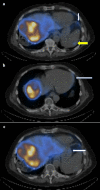

Figure 2

Figure 2. Axial SPECT images demonstrating small amounts of activity in the diaphragm (a, white arrow), spleen (a, yellow arrow), pericardium (b, white arrow), and stomach (c, white arrow).

SPECT: single-photon emission computed tomography.